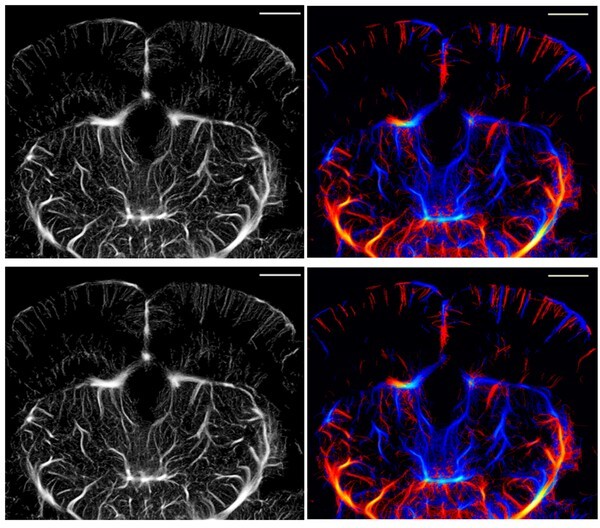

유재석·현정호 교수팀은 이러한 문제를 해결하기 위해, 초음파 신호 중 핵심 정보만 남기고 불필요한 데이터를 과감히 줄이는 새로운 분석 방식을 고안했다. 연구팀은 신호의 ‘유효 대역폭’을 약 67%로 줄이고, 혈관의 구조를 그리는 데 꼭 필요한 정보만 효율적으로 추출하는 ‘ULM-Lite’ 방식을 고안했다. 그 결과, 데이터 용량은 줄었지만 영상의 선명도는 거의 변함이 없었고, 처리 속도는 훨씬 빨라졌다.

이번 연구의 핵심은 기존 초음파 장비를 그대로 쓰면서도 데이터를 크게 줄였다는 점이다. ‘ULM Lite’는 초음파 신호 중 꼭 필요한 정보만 남겨 데이터량을 약 3분의 1로 줄였지만, 화질은 기존과 거의 같다. 별도 장비 교체 없이 적용할 수 있고, 영상 처리 속도도 약 30% 빨라졌다. 또 수술이나 형광물질 없이 비침습적으로 뇌 전체를 선명하게 볼 수 있어, 뇌 연구와 질환 진단의 효율성을 크게 높였다. 뇌의 자극 치료와 행동 변화 관찰을 위한 도구로 활용 가능성이 높다.